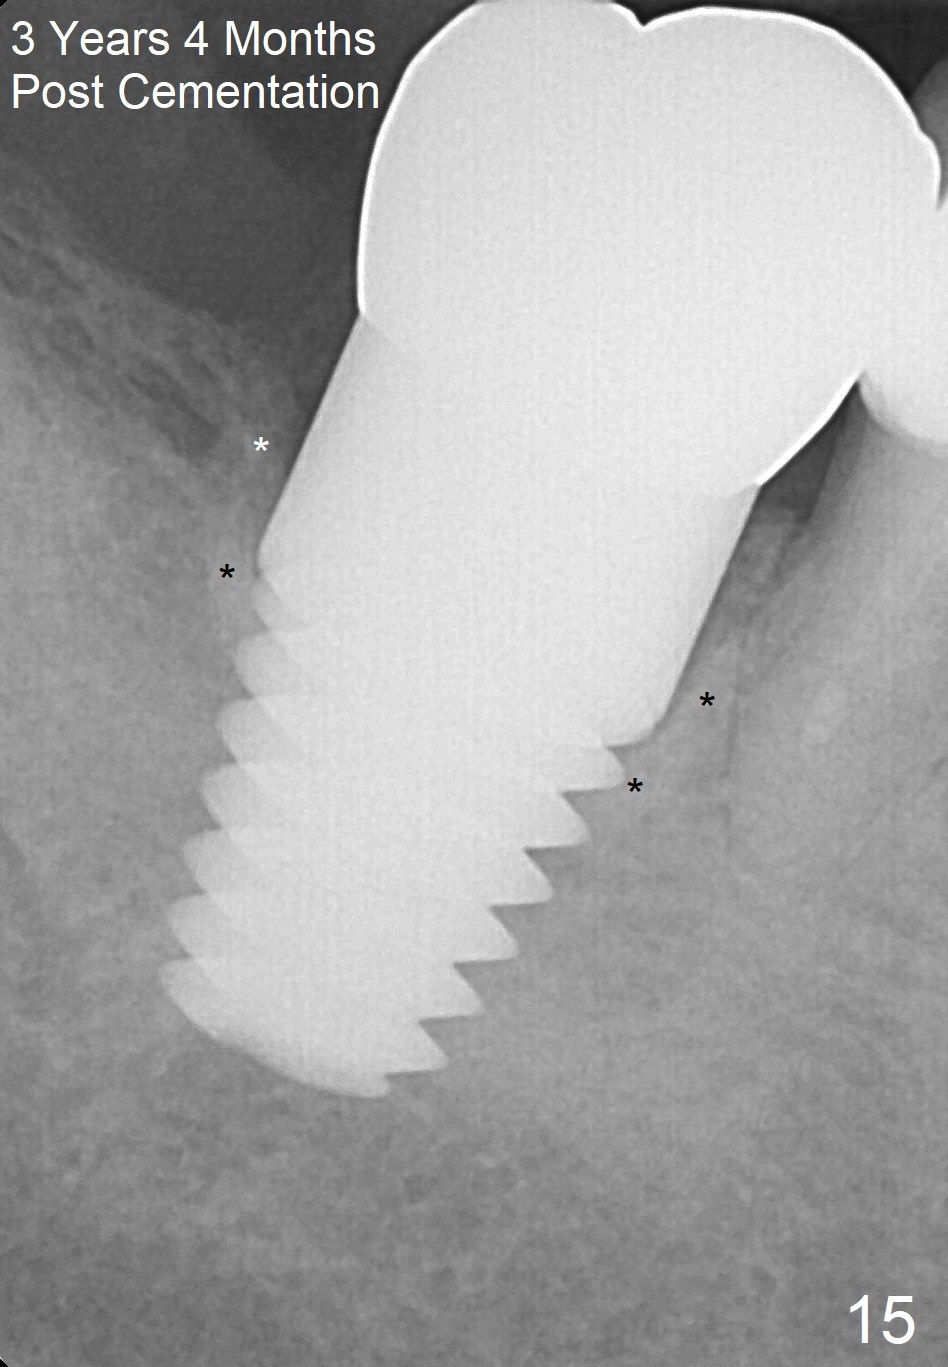

The patient returns for final restoration 5.5 months postop; it appears that the distal gap has disappeared (Fig.13 *). There is no bone loss 26 months post cementation (Fig.14). The lamina dura-like dense bone forms coronally 3 years 4 months post cementation (Fig.15 *). The 8 mm implant remains buried in the bone 5 years 4 months post cementation (Fig.16).